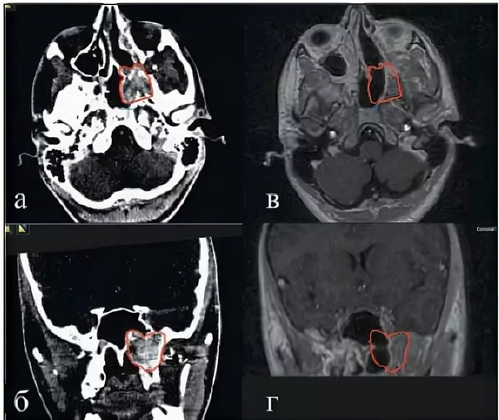

Фото: минздрав Владимирской области

Врачи ЛОР отделения ОДКБ поставили серьезный диагноз ребенку - юношеская ангиофиброма основания черепа. Это доброкачественная, но агрессивно растущая опухоль, угрожающая смертью пациенту, если ее не лечить. 15-летний подросток поступил с жалобами на затруднение дыхания и массивные носовые кровотечения.

Остановка таких кровотечений возможна только перевязкой сонных артерий, рассказали в пресс-службе минздрава Владимирской области. После постановки диагноза медики приняли решение направить мальчика в Федеральный центр имени Рогачева, где состоялась операция. Сейчас пациент уже выписан оттуда и проходит лечение снова в ЛОР отделении ОДКБ.